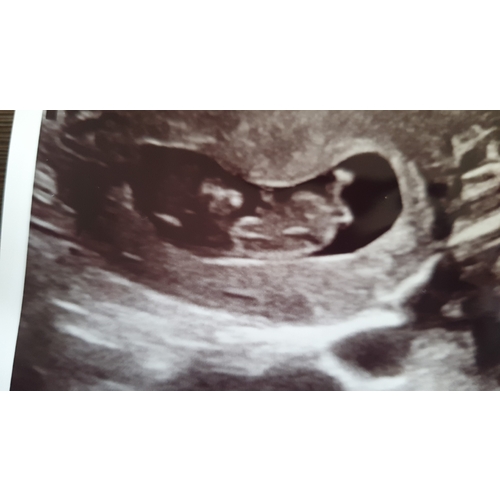

Hi allemaal 😘 Wat denken jullie bij mij 🙊 Dit is zó spannend! (12w) ♥️

Misschien kan dit ook helpen? De gynaecoloog zei dat ze het nog niet kon bevestigen 🤷🏻‍♀️ Maar als je het mij vraagt 😅 Ik zal geduldig wachten op de resultaten van mijn NIPT test 😘